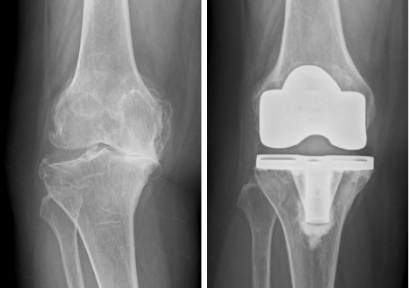

■人工膝関節置換術